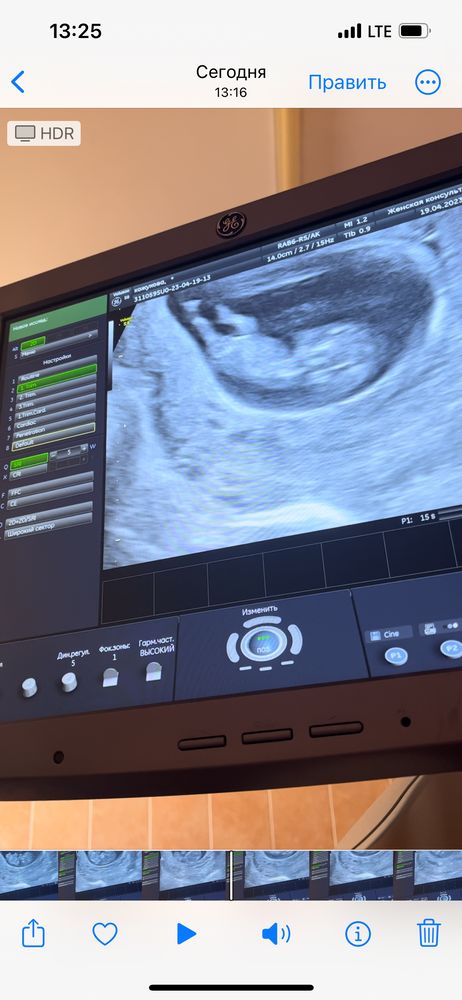

Узи в 10 н 3 д

19.04 был прием, предложили узи для моего успокоения😂видимого приеме создаю впечатление очень тревожной беременной.

Все хорошо, тьфу тьфу, ктр 42.6мм, по размерам сказали на 11н 1д, видно ножки, ручки, движения, чсс 167.

Там такие танцы были на экране, так удивительно, пока не чувствуешь вообще сложно себе все это представить.